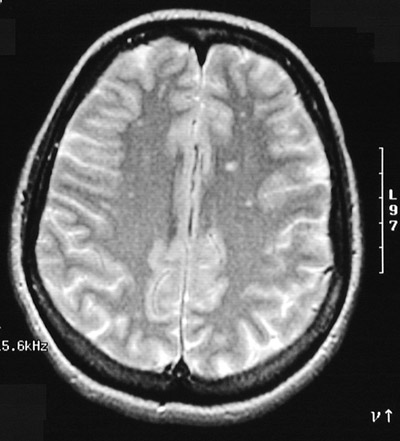

The T2 weighted MRI scans in axial view above and below demonstrate multiple small bright foci on the left as well as on the right that represent small areas of plaque formation in a patient with an exacerbation of multiple sclerosis.